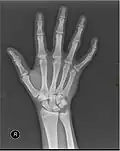

X-ray

X-ray image of right hand with thumb on left. -

Multiple fractures of the metacarpals (aka broken hand). (Right hand shown with thumb on left.) -